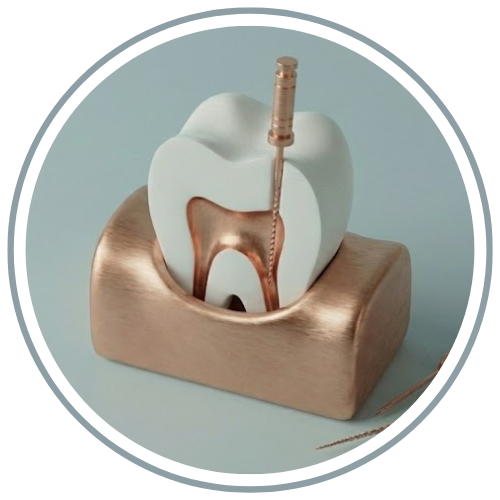

تجربه دردناک کشیدن دندان مربوط به گذشته است. در کلینیک دندانپزشکی مهر امیرآباد، ما با استفاده از مدرنترین داروهای بیحسی و تکنیکهای جراحی آرواماتیک (کمتهاجمی)، دندانهای آسیبدیده یا نهفته را خارج میکنیم. هدف ما نهتنها رفع درد، بلکه حفظ ساختار استخوان فک برای جایگزینیهای احتمالی آینده (مانند ایمپلنت) است.

- جراحی دندان عقل نهفته: تخصص در خارج کردن دندانهای عقل پیچیده و نهفته بدون آسیب به اعصاب فک.

۱. معاینه و رادیوگرافی: بررسی دقیق موقعیت ریشه دندان با عکس OPG یا CBCT برای جلوگیری از آسیب به عصب.

۲. بیحسی موضعی: تزریق آرام و دقیق ماده بیحسی؛ تا زمانی که ناحیه کاملاً بیحس نشود، کار شروع نمیشود.

۳. جراحی و خارج کردن دندان: پزشک با ابزارهای مخصوص (الواتور و فورسپس) دندان را لق کرده و خارج میکند. در موارد جراحی، ممکن است نیاز به برش کوچک لثه باشد.

جراحی دندان عقل نهفته

دندانهای عقل اغلب به دلیل کمبود فضا در فک، به صورت نهفته یا نیمهنهفته رشد میکنند. این وضعیت میتواند باعث درد، تورم، بوی بد دهان و کج شدن سایر دندانها شود. جراحی دندان عقل در کلینیک مهر توسط متخصصین جراحی فک و صورت با حداقل برش و دوره نقاهت کوتاه انجام میشود.